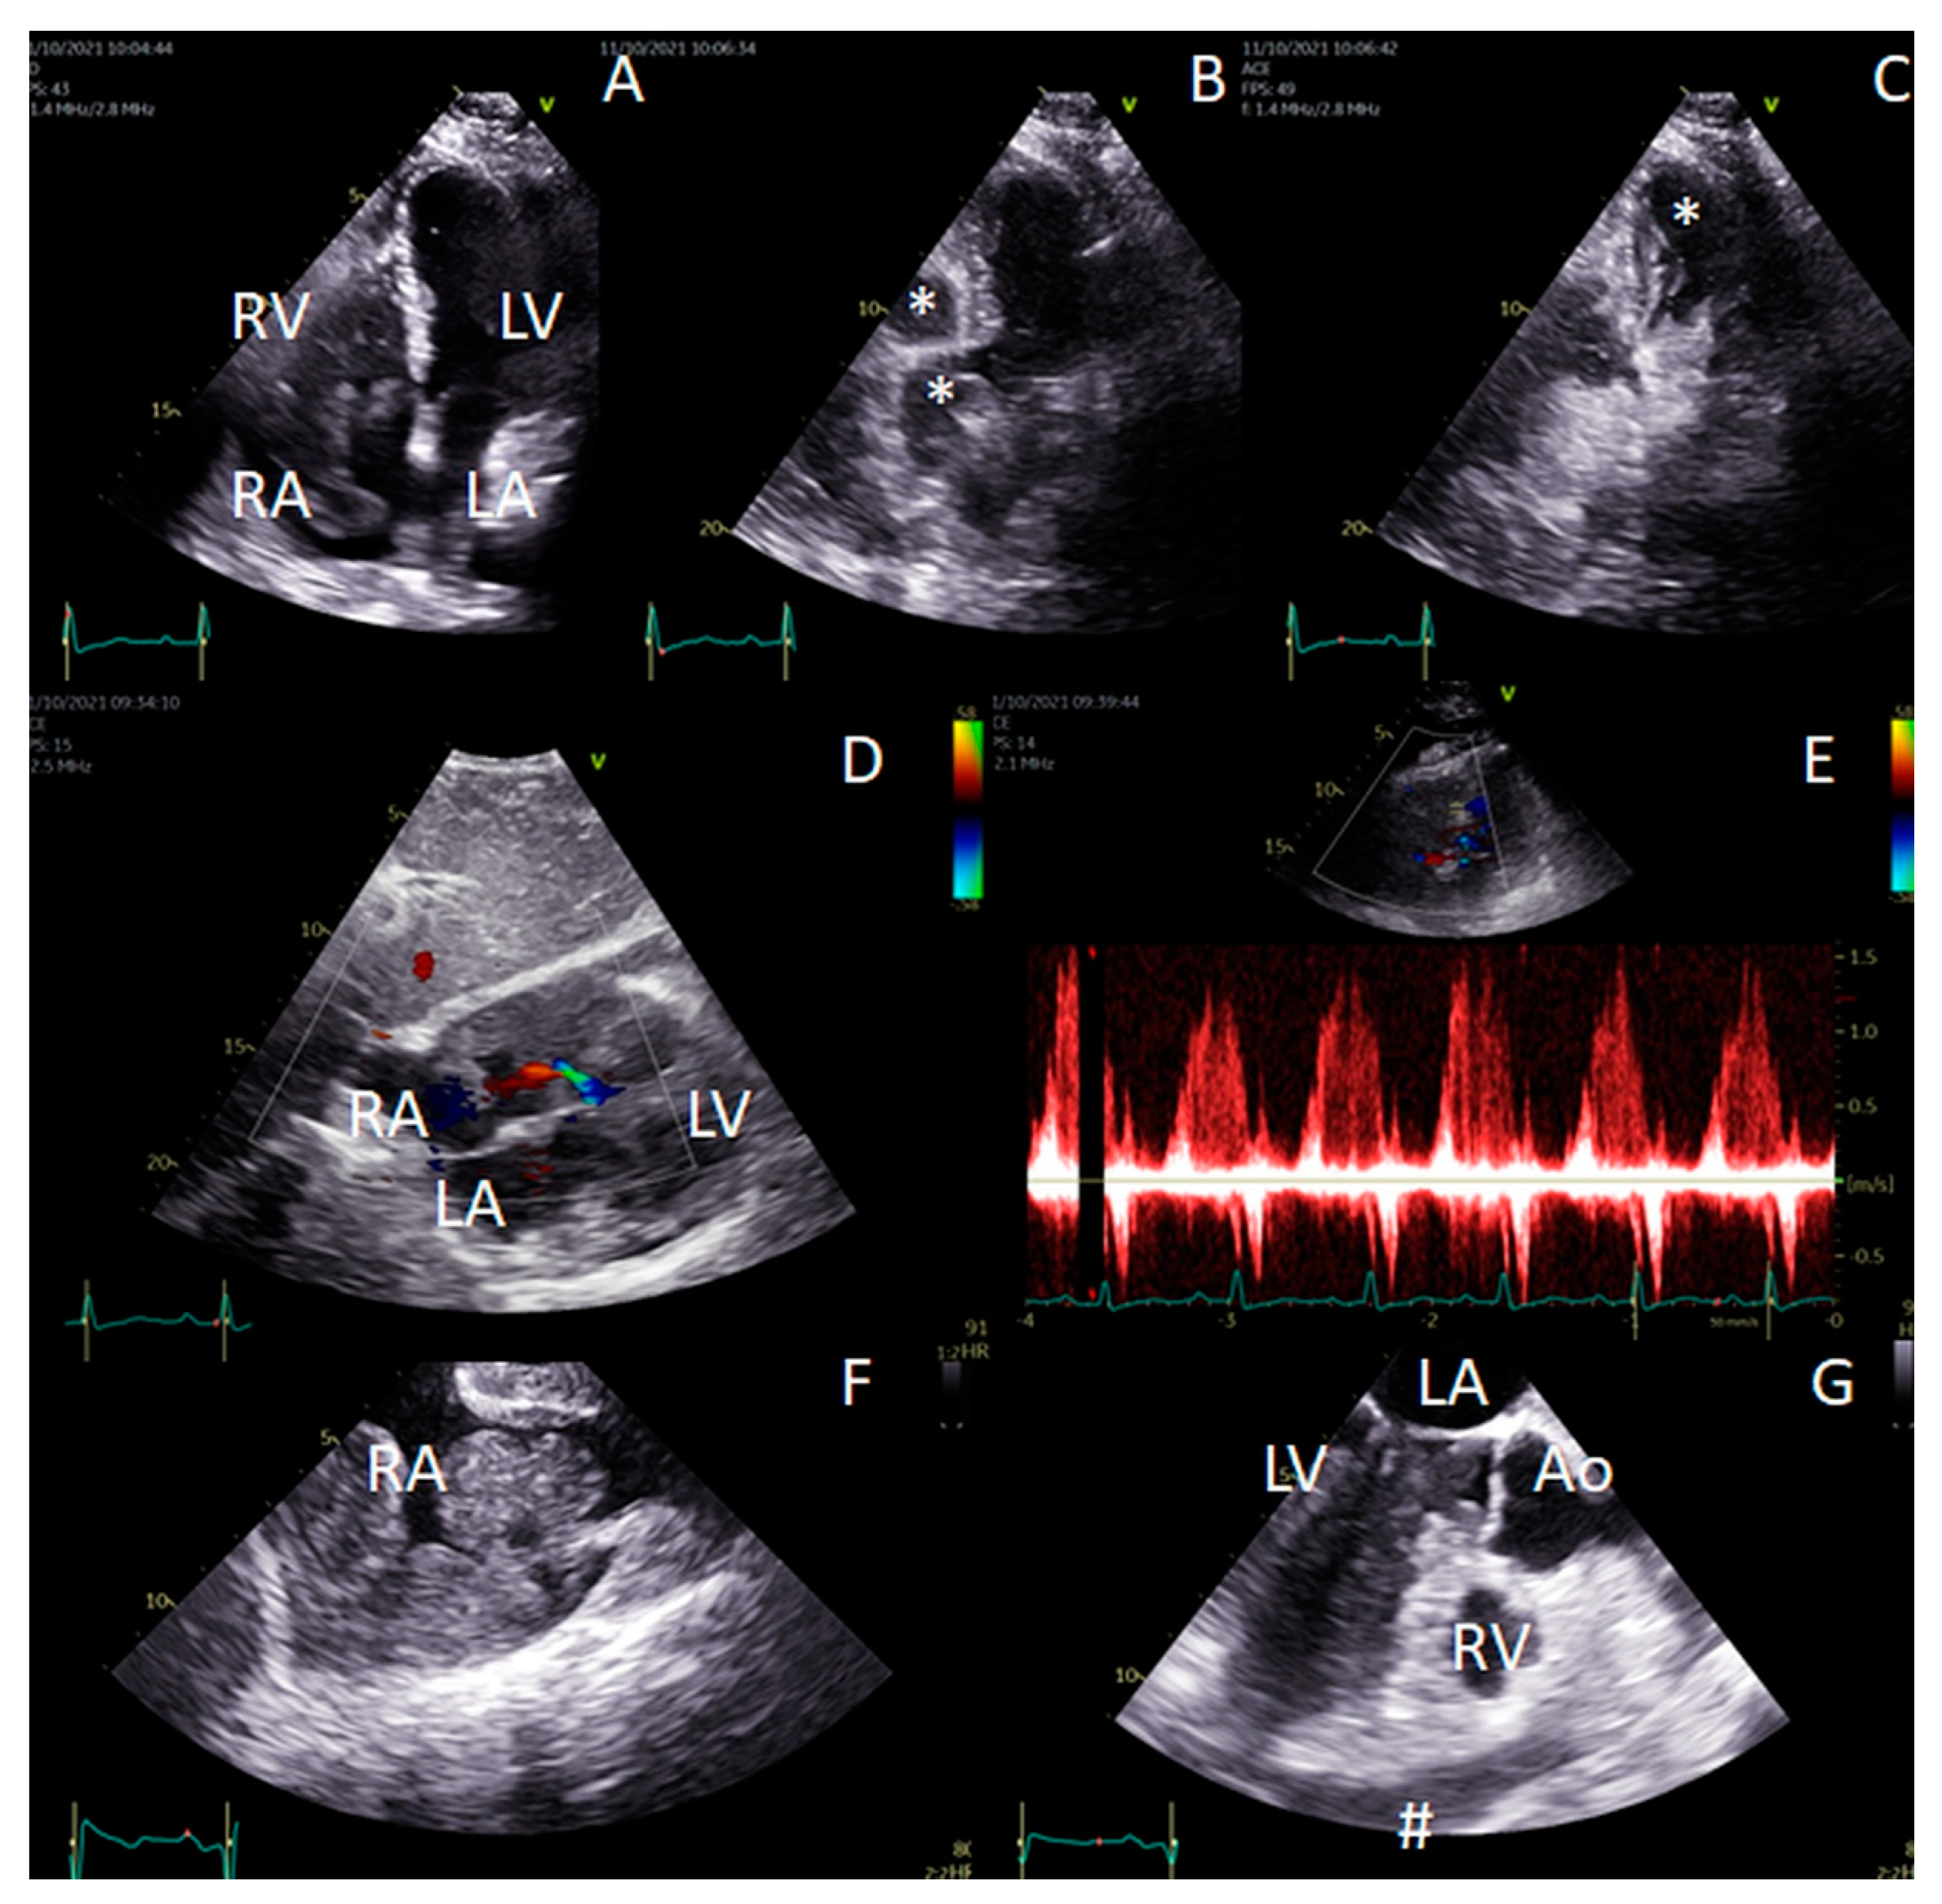

| Robak et al. 2022 [34] | 57/W | SLL diagnosed 20 yrs prior to cardiac infiltration | Increasing fatigue and tachycardia, Echocardiogram—multiple ovoid, partly mobile intracardiac masses up to 45 mm size, identified in all cardiac cavities, the CT image demonstrated adenopathy in the mediastinum, enlargement of the cardiac silhouette and hypodense areas in the right atrium, right ventricle and left ventricle. Heart biopsy and BM trephine biopsy indicated a diagnosis of SLL. | RB, venetoclax + rituximab, R-CHOP | Excellent cardiac response after BR and venetoclax plus R with RT in BM |